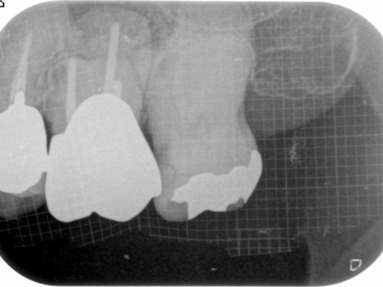

この組み合わせ3枚の写真はCT画像です。左の写真と真ん中の写真は同じものですが、わかりやすいように色を付けています。

黄色の線は根の外形です。

オレンジ色は、過去の根管治療の不備によりできた骨が吸収してしまった部分です。

赤の点線は、病変により破壊されてしまった上顎洞底(上顎洞と口の中を隔てる骨)の骨です。

水色は、それによって肥厚(腫れあがった)してしまった上顎洞粘膜です。

このような状態は2次元のレントゲンでは診断すらできません。CTを撮影することにより正確に診断ができ、それにあった処置法を選択する事が可能になります。

一番右の写真は処置直後で、MTAを用いて根管充塡し、治癒を待ちます。